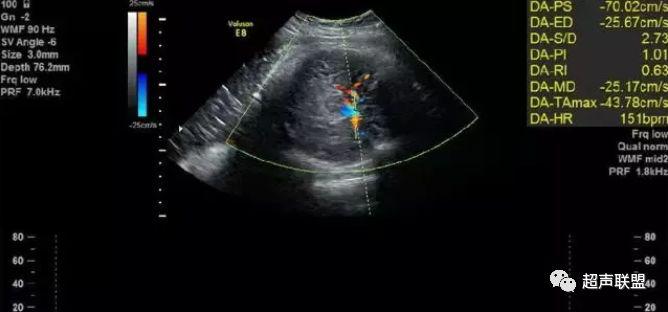

3 胎儿静脉导管

当右心负荷增大,心功能失代偿时,静脉回流受阻,静脉导管a波收缩期流速下降,血流消失甚至倒置。

5、静脉导管:a波消失或反向(见于严重的胎儿宫内缺氧);

7、宫内缺氧时肾动脉及腹主动脉的血流频谱为舒张末期血流的降低,RI及PI值会逐渐升高,若血流再分配严重时其舒张末期的血流将会消失甚至出现反向血流的产生。同时静脉导管也会反映缺氧时心脏功能的情况,当胎儿右心负荷增大,心脏功能失代偿时,静脉回流将会受阻,静脉导管心房收缩期流速逐渐下降,其血流消失甚至于血流倒置。

3、静脉导管a波反向或消失;

图5 胎儿宫内正常静脉导管

图6 胎儿宫内缺氧时静脉导管a波反向